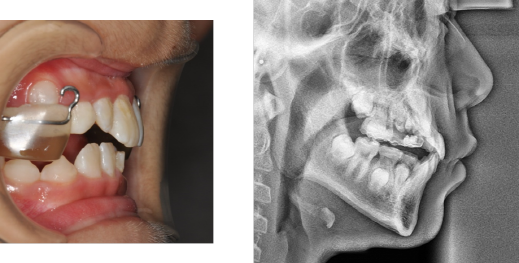

악궁확장장치와 페이스마스크 장치를 이용하여

위 턱을 넓히고 위 턱을 앞으로 끌어내 주며

아래턱이 나오는 힘을 위 아래로 분산시켜 줍니다.